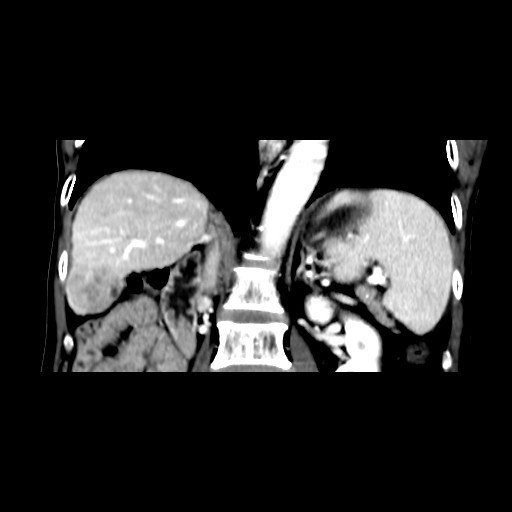

查体:肝脏剑突下4cm可触及,质中。移动性浊音可疑阳性,肠鸣音正常。 辅助检查:外院查MR示:肝脏右叶后下段团块影,直径约3.6cm,考虑肝癌;肝硬化、脾大,多量腹水,考虑门静脉高压。

诊断:1、肝细胞癌 2、肝炎后肝硬化(乙肝)、门静脉高压、脾大、腹水。 治疗:入院复查CT示:1、肝S6段结节型肝癌。2、结节型肝硬化;门脉高压,食管胃底静脉、胃管状静脉、脾静脉曲张;脾稍大;少量腹水。 遂排除手术禁忌症,于全麻下行肝S6段肝癌切除术,术后病理示:(肝S6段肿物)形态结合免疫组化,符合高~中分化肝细胞性肝癌,未见确切脉管内癌栓形成;“切缘”未见癌;周围肝组织呈结节性肝硬化改变。免疫组化结果(⑦):Hep(+),Gly-3(部分+),CK7(-),CK19(-),CD34(肝窦毛细血管化),Ki-67(平均15%+)。术后继续患者肝功能逐渐恢复,腹水逐渐吸收。